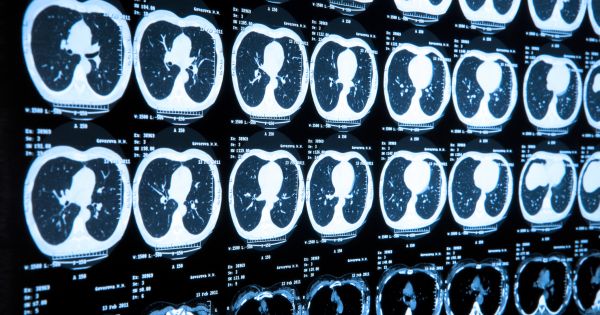

Cognitive system can now predict your death from CT scan June 7, 2017 by timbatchelder, posted in Knowledge Management AI can now predict the potential a patient will die within 5 years. Source: An AI Can Now Predict How Much Longer You’ll Live Rate this:Share this: Email a link to a friend (Opens in new window) Email Share on Tumblr (Opens in new window) Tumblr Print (Opens in new window) Print Share on Facebook (Opens in new window) Facebook Share on LinkedIn (Opens in new window) LinkedIn Share on X (Opens in new window) X Share on Pinterest (Opens in new window) Pinterest Share on Threads (Opens in new window) Threads Share on Mastodon (Opens in new window) Mastodon Share on Nextdoor (Opens in new window) Nextdoor Share on X (Opens in new window) X Share on Bluesky (Opens in new window) Bluesky Like Loading... Related